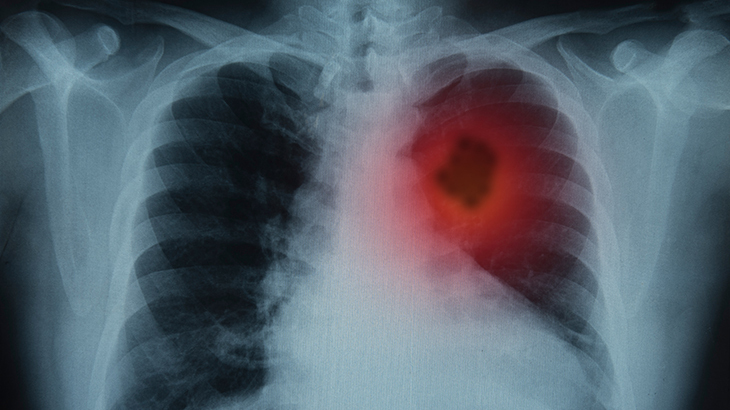

Akciğer kanseri

Akciğer kanserine karşı yüksek riskli kişilerin akciğer taraması yaptırması öneriliyor. Hayat boyu 30 paket.yıl (günde içilen paket sayısı ile toplam içilen yıl çarpılarak hesaplanır) ve daha fazla içimi olan (Örneğin; günde 2 paket sigara içen ve 20 yıl sigara içmiş kişi: 2x20=40 paket.yıl), son 15 yıllık dönemde aktif sigara içmiş olan ve 55-74 yaşları arasındaki kişilerde yılda bir defa düşük doz tomografi ile tarama yapılması erken teşhiste büyük önem taşıyor. 15 yıldan uzun süredir sigarayı bırakmış olanlarda tarama testi önerilmiyor. Bu tarama testi ile akciğer kanserinden ölüm oranlarının yüzde 20 oranında azaldığı belirtiliyor.